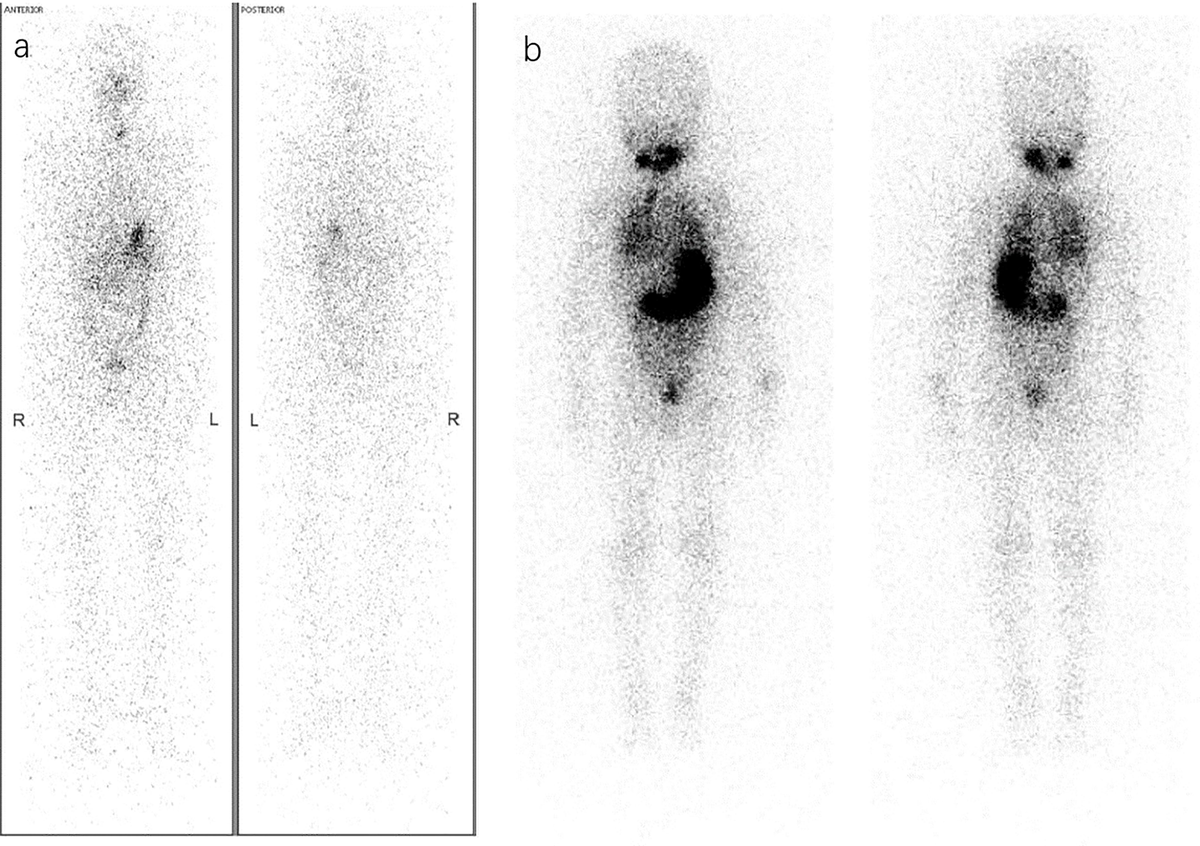

Thyroid Cancer Explore vol.1 no.2(2015 「Thyroid Cancer Expl Advances in Functional Imaging of Differentiated Thyroid Cancerの詳細情報

Advances in Functional Imaging of Differentiated Thyroid Cancer。Improving the diagnosis of thyroid cancer by machine。Frontiers | Active surveillance in differentiated thyroid。

ThyroidCancerExploreVol.1No

「ThyroidCancerExpl

ThyroidCancerExploreVol.1No

「ThyroidCancerExpl